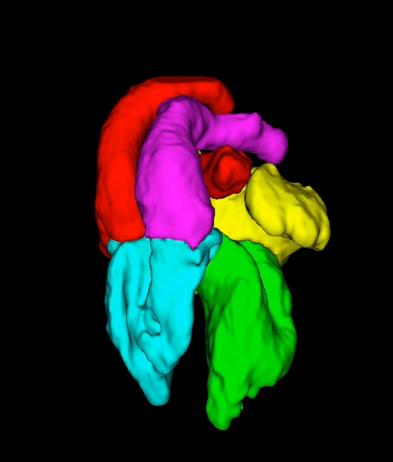

3D printing of heart models is very useful for planning a surgical or cardiological procedures. However, such processes take a considerable amount of time to complete. We are working on the development of a fast and effective strategy for the segmentation of CT or cardiac MRI to facilitate 3D printing.